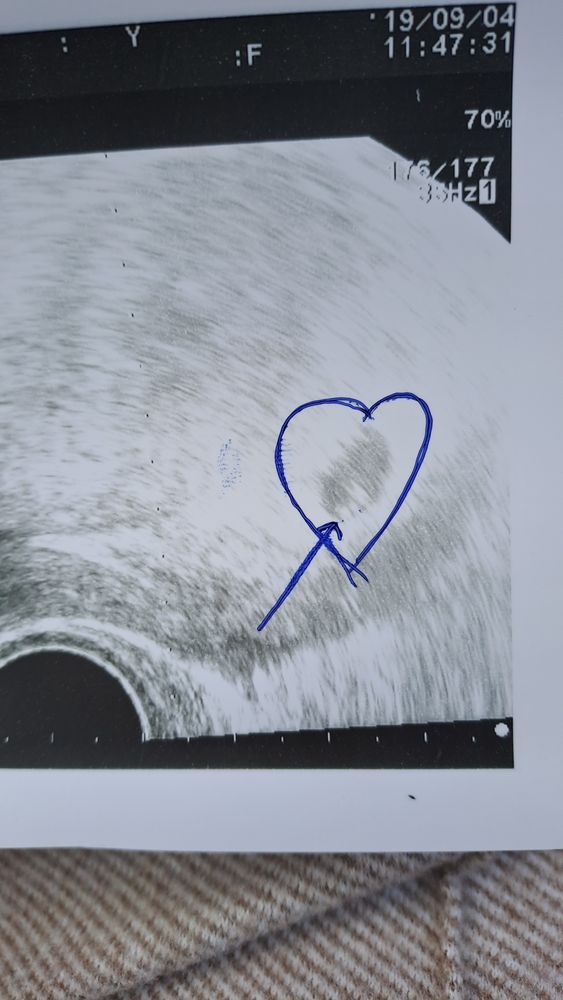

Первое узи😇

Изображение

Такое волнительное наше первое узи☺️

По месячным сегодня 02.09 ровно 7 неделек, но по узи немного отстает, скорее всего была поздняя овуляция. Поставили 5н6д🧡